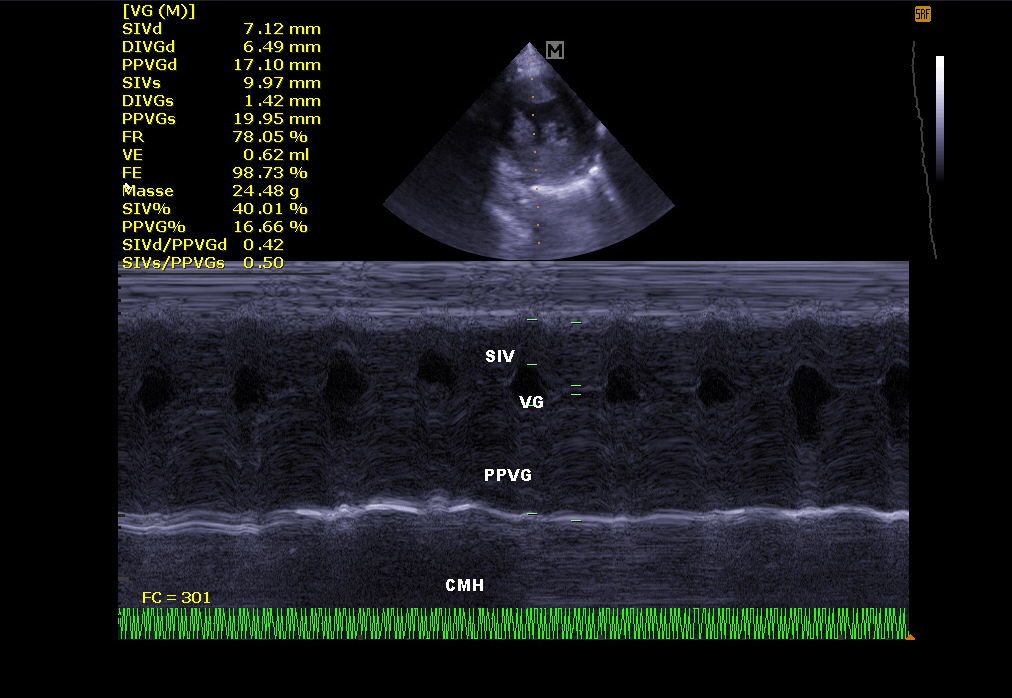

Echocardiography:

It makes it possible to visualize the different parts of the heart (walls, cavities, valves) and to identify any anomalies that prevent correct cardiac functioning. In case of heart failure, echocardiography also allows regular monitoring of cardiac morphology. It is then easier to readjust the treatment in place.